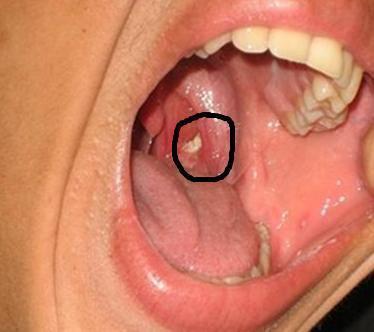

扁桃体结石最常见的症状是咽痛和口臭。 如果结石比较小,可能感受不到明显的症状,或者仅能感到咽喉部轻度的不适,多数情况下会有明显的口臭; 如果结石比较大,可能会有明显的咽部异物感,并且有反复咽痛。 个别人会有耳朵发闷、耳朵疼痛等症状 要想预防扁桃体结石,首先要了解它是怎么来的。 扁桃体结石好发于扁桃体上隐窝(就是你看到的扁桃体上的坑坑洼洼),是由于扁桃体炎症或异物堵塞隐窝口而形成的结石,多为白色、黄色或灰黄色。 扁桃体结石常见于这几类人群: 1 扁桃体炎症患者 2四、酸梅6克,青果 (橄榄)25克,白糖适量。 将酸梅及青果放人砂锅内浸泡半天,然后煎煮,服时加白糖调味,适用于扁桃体炎症的治疗。 五、选择400克的蒲公英、金银花,0克的薄荷,100克的甘草,50克的胖大海,30克的淀粉。 先取薄荷、甘草、胖大海及